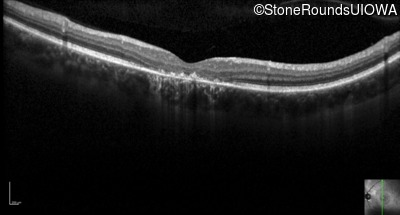

Optical Coherence Tomography - Left - 20/100 sc

Exemplar / OCT Stack